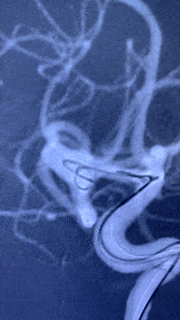

术前影像

该前交通动脉瘤,为宽颈,且与两侧A2均关系密切,载瘤血管约为2.1mm。